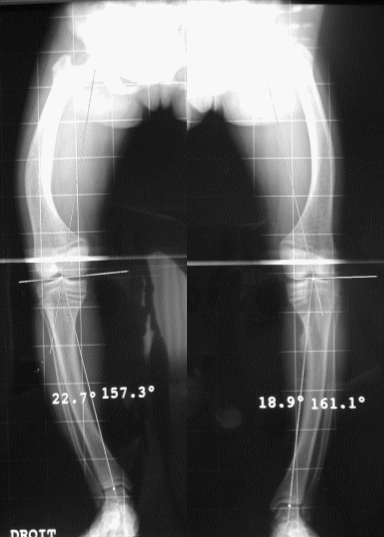

Le bilan de base est radiographique : il faut demander des incidences précises tout en sachant prendre du recul vis à vis du compte-rendu.

La radiographie à demander est un cliché des membres inférieurs debout de face stricte, en appui symétrique, rayons centrés sur l’horizontale, joignant la pointe des rotules, le tout sur une grande cassette de 90 cm (vision depuis les épines iliaques antéro-supérieures jusqu’aux calcanéums).

La déviation angulaire globale (DAG), représentée

par l'angle CIC', mesure l'importance de la désaxation.

Il faut savoir qu'il existe une déviation angulaire physiologique(DAP)

: elle est de 3° de valgus physiologique chez la femme, et de 2°

chez l’homme.

Il est donc nécessaire de corriger la déviation

calculée sur la radiographie en tenant compte de la déviation

natuelle, de la façon suivante.

Déviation angulaire corrigée (DAC) :

DAG – DAP en cas de valgus

DAG + DAP en cas de varus